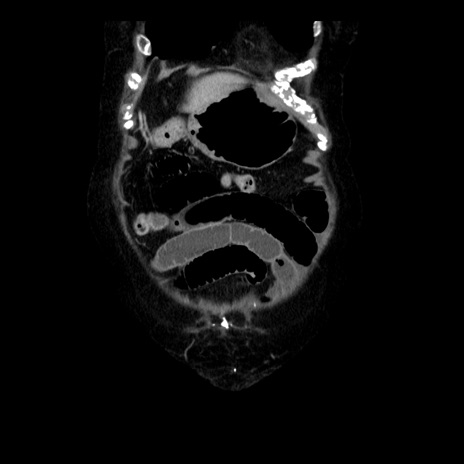

横断像